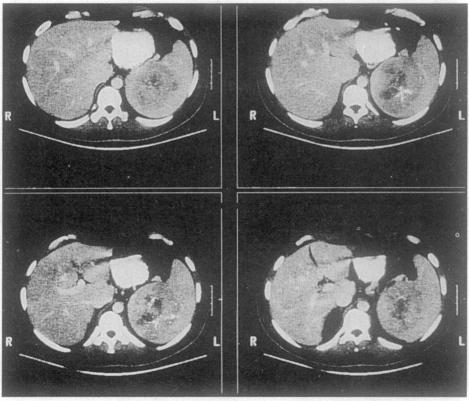

Increased erythrocyte sedimentation rate and a splenic mass.